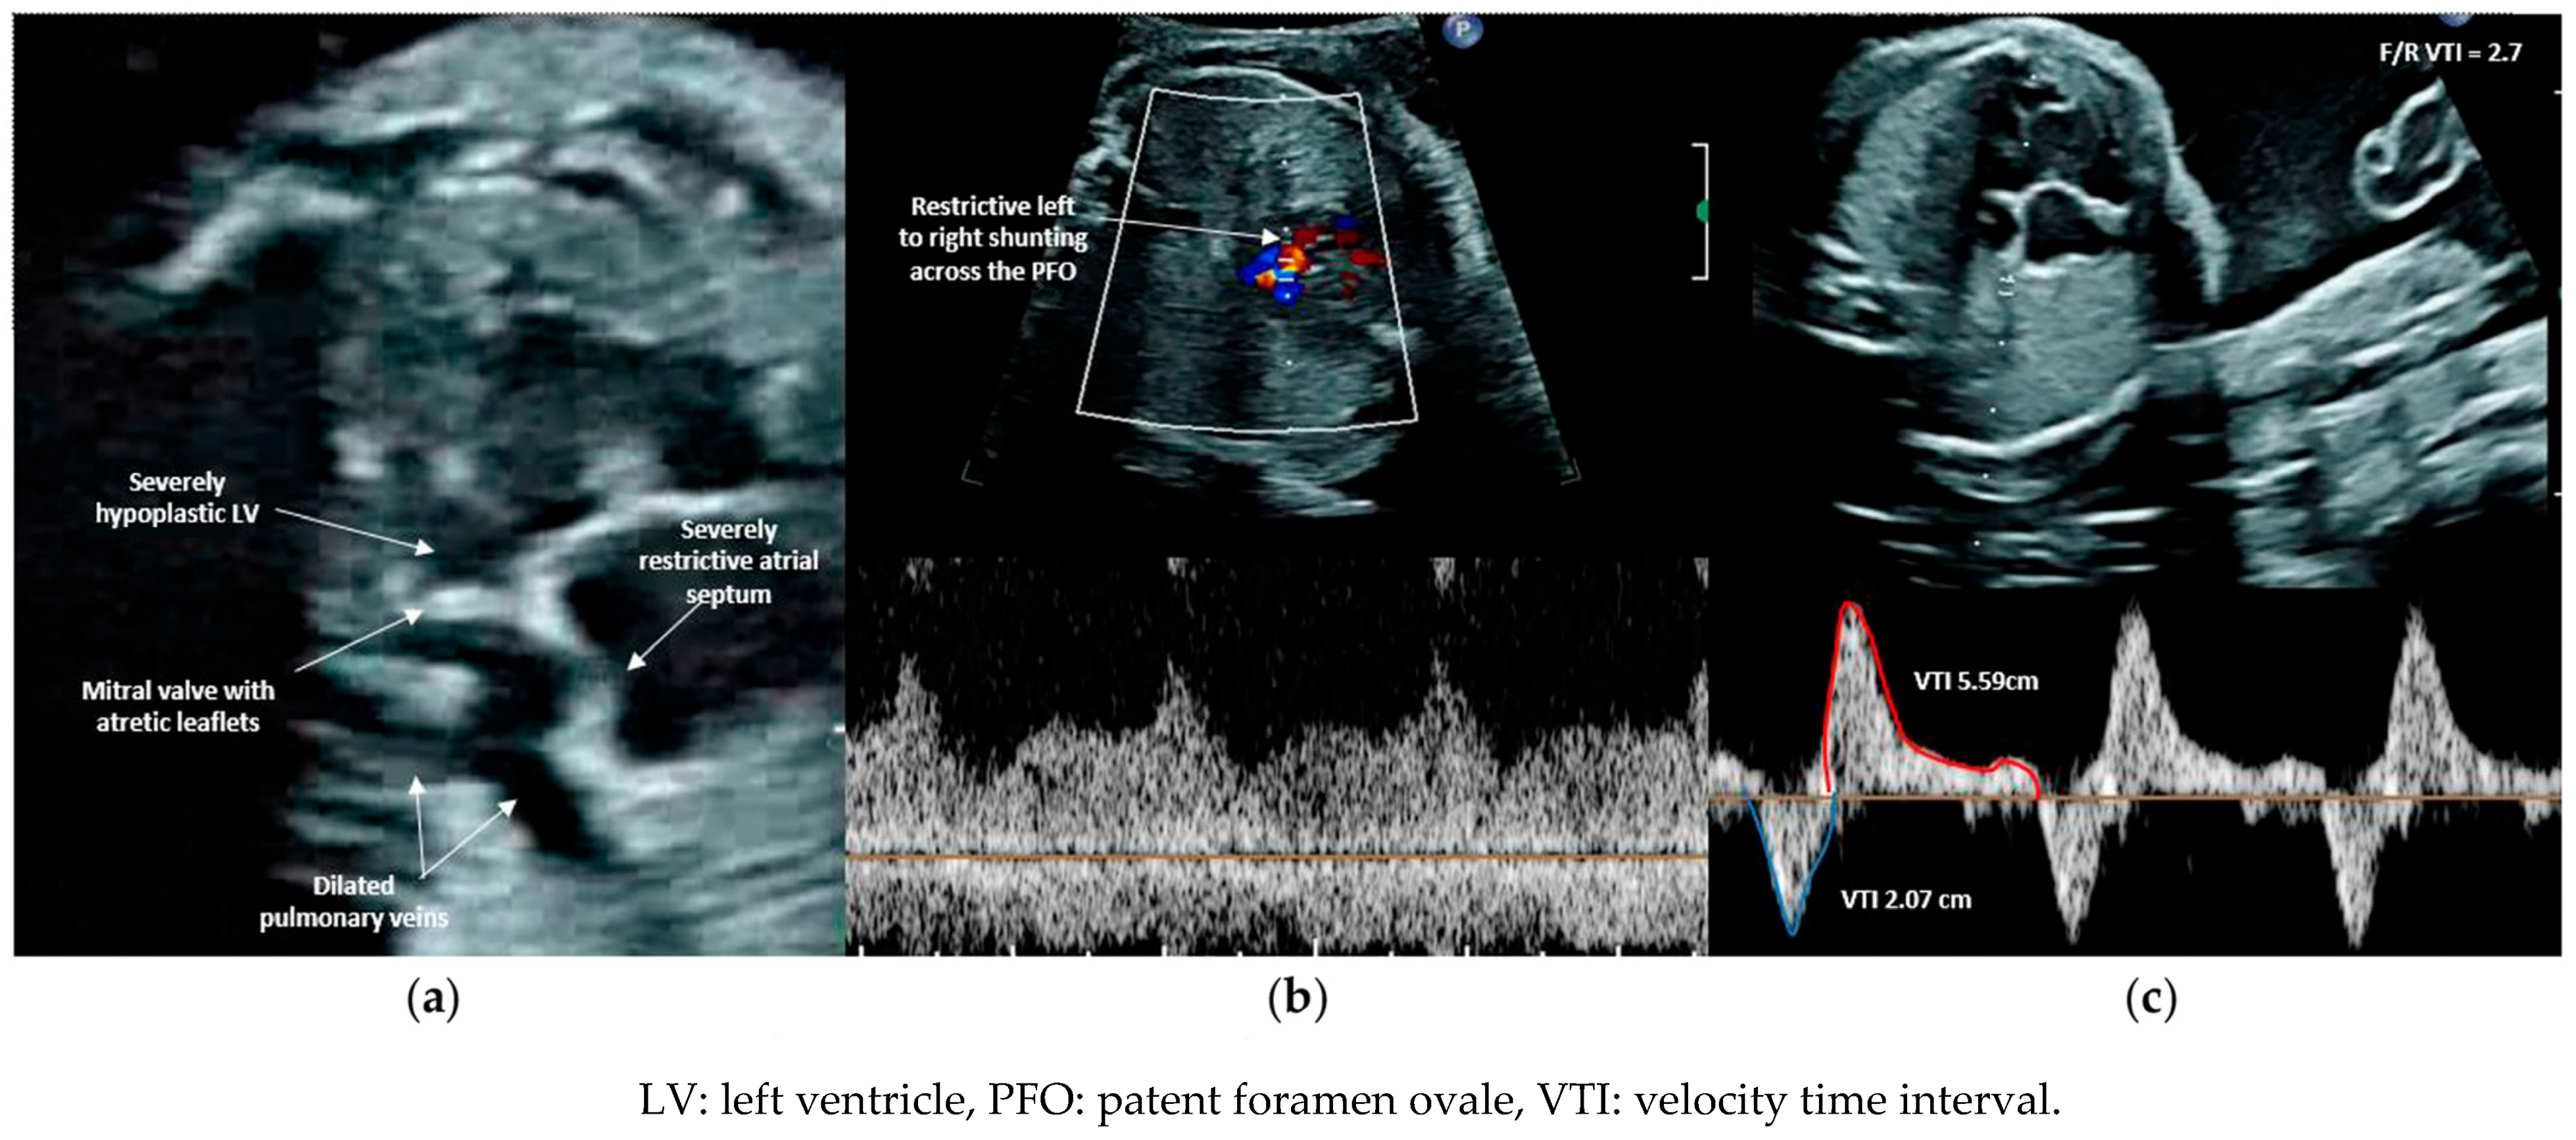

3. Atrial Septal Intervention for Hypoplastic Left Heart Syndrome (Hlhs) with Highly Restrictive or Intact Atrial Septum (R/Ias)

3.1. Patient Selection

3.2. Procedural Technique